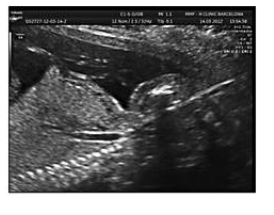

При тщательной оценке легочной ткани была выявлена расширенная на всем протяжении трахея (рис. 4) и расширенные бронхи (рис. 5).

Рис. 4. Парасагиттальный скан. Расширенная до уровня обструкции трахея.

Рис. 5. Поперечный скан. Расширенное бронхиальное дерево.